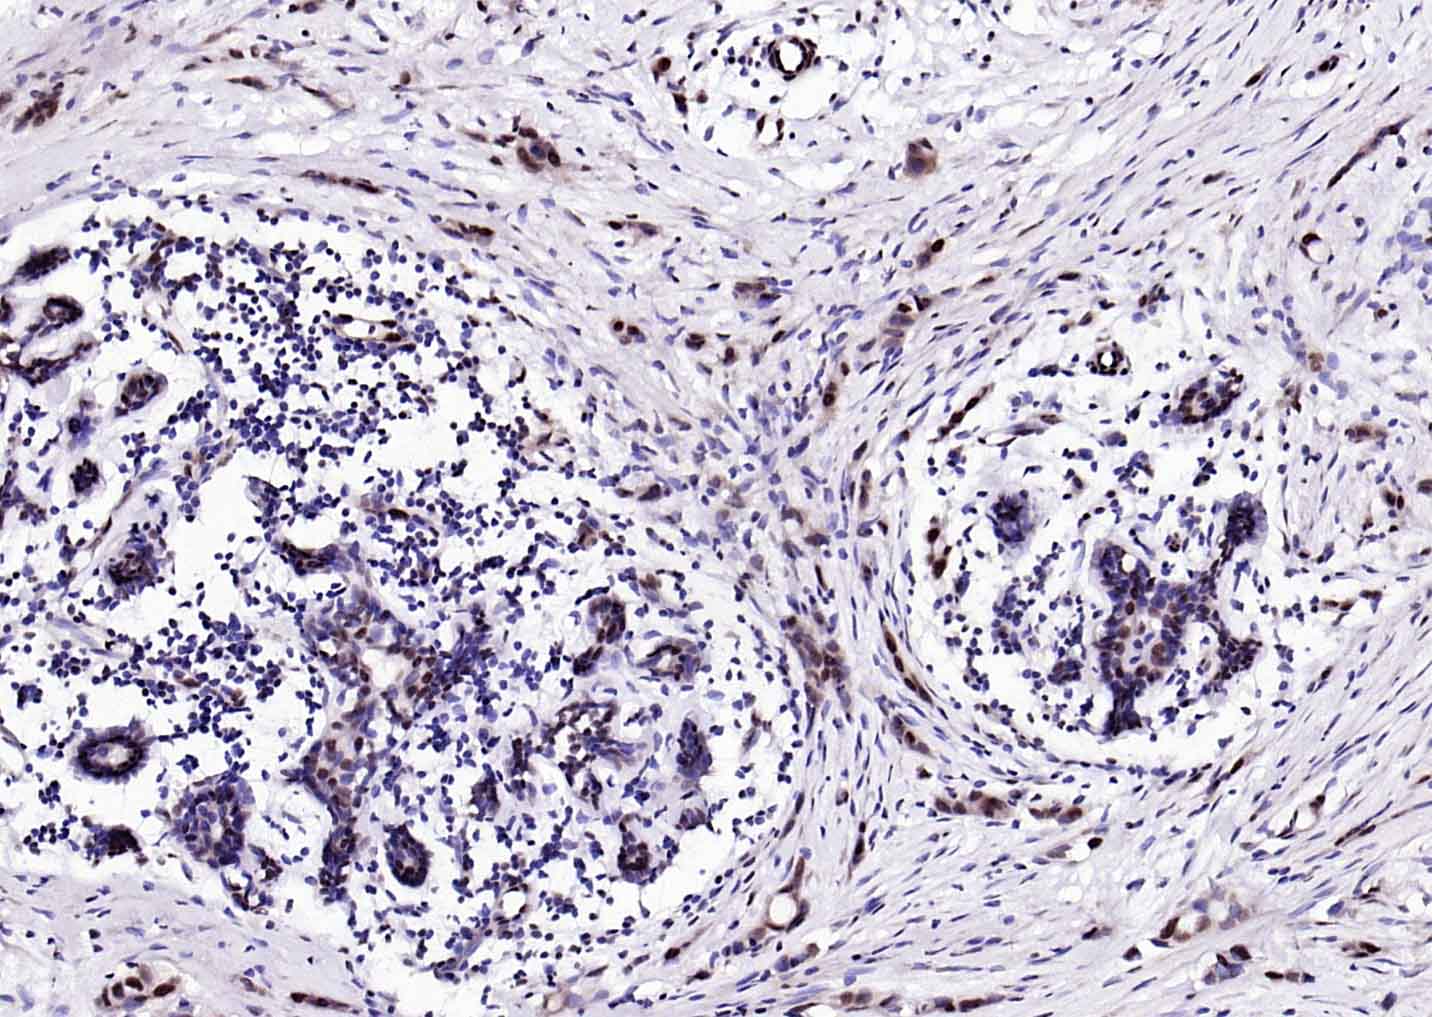

Paraformaldehyde-fixed, paraffin embedded Human Colon Cancer; Antigen retrieval by boiling in sodium citrate buffer (pH6.0) for 15 min; Antibody incubation with ESR2 Polyclonal Antibody, Unconjugated (bs-0116R) at 1:200 overnight at 4°C, followed by conjugation to the SP Kit (Rabbit, SP-0023) and DAB (C-0010) staining.

Paraformaldehyde-fixed, paraffin embedded Human Cervical Cancer; Antigen retrieval by boiling in sodium citrate buffer (pH6.0) for 15 min; Antibody incubation with ESR2 Polyclonal Antibody, Unconjugated (bs-0116R) at 1:200 overnight at 4°C, followed by conjugation to the SP Kit (Rabbit, SP-0023) and DAB (C-0010) staining.